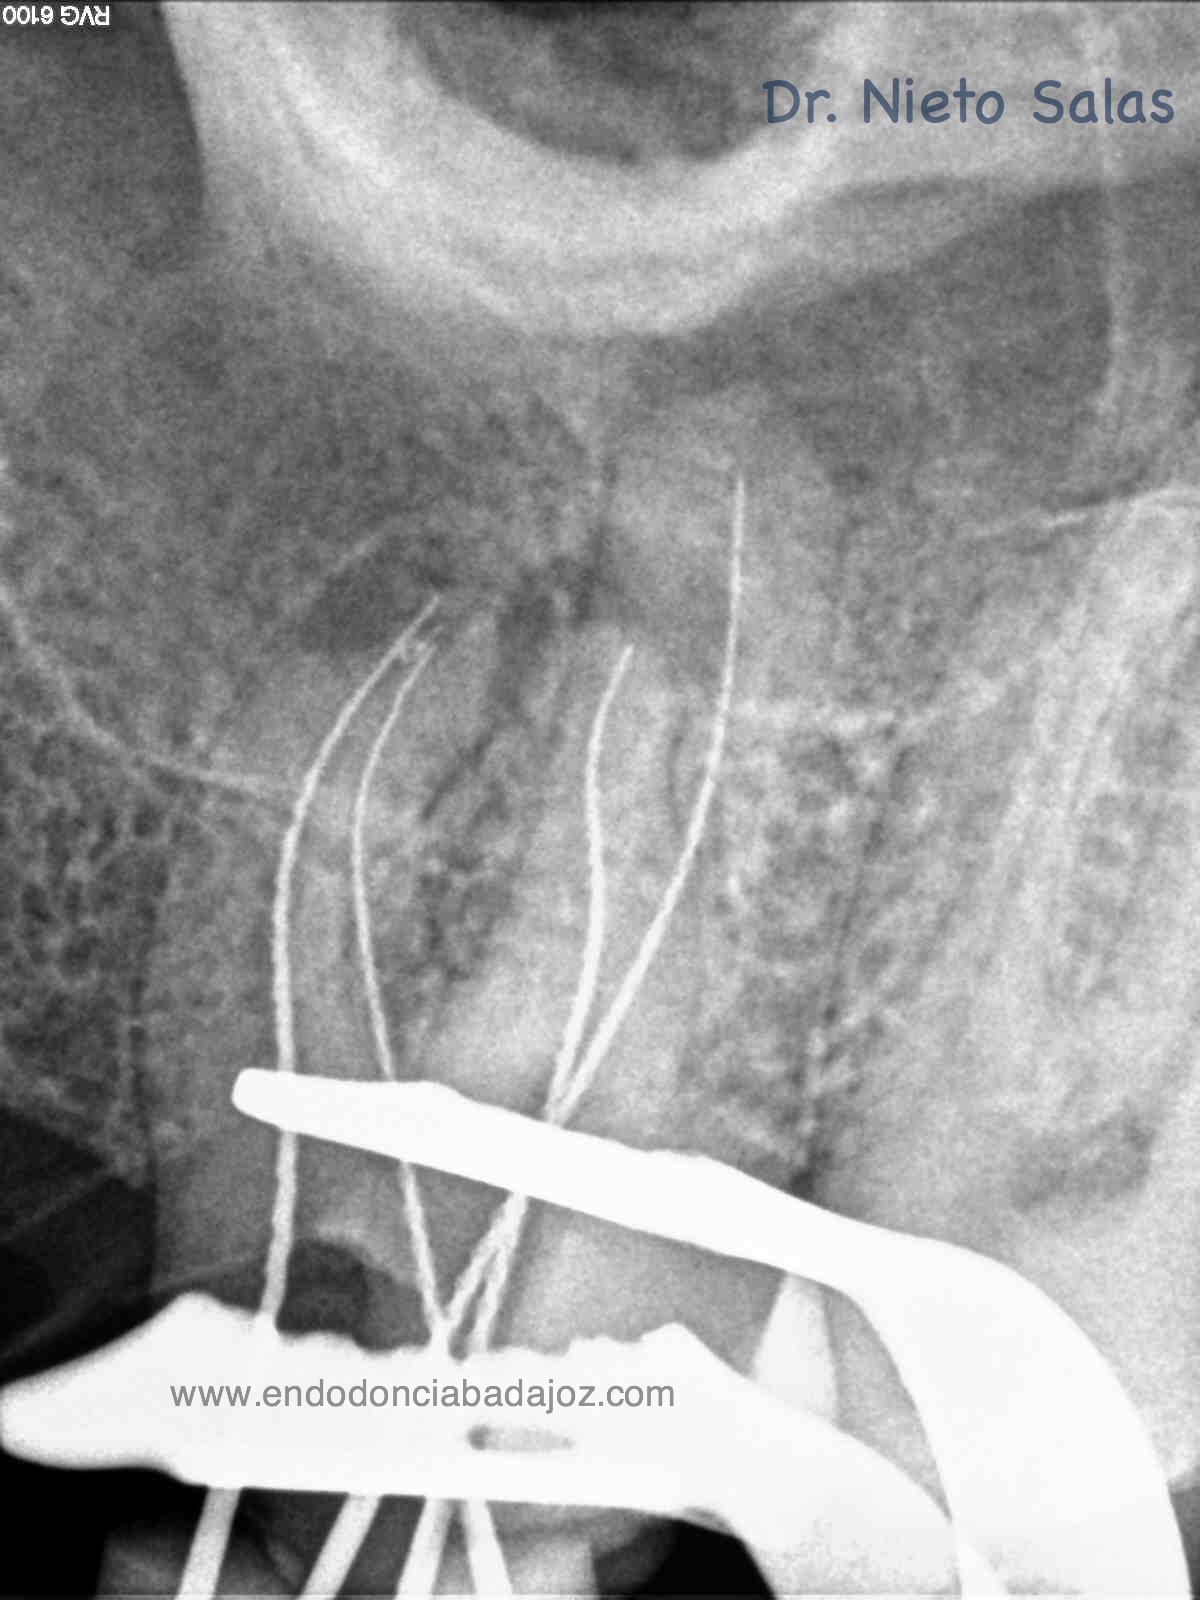

Os presento unos casos de varios molares superiores, con tres conductos mesiovestibulares con un foramen o con dos.

Una vez que tenemos medidas, obturamos los conductos:

No es habitual en nuestra práctica casos como estos, pero os pongo algunos más:

Sabemos que unas de las piezas que más fracasan, son estas piezas, pues, sin la ayuda de magnificación, es muy probable que dejemos alguna zona del sistema sin limpiar y mucho menos, obturarla.